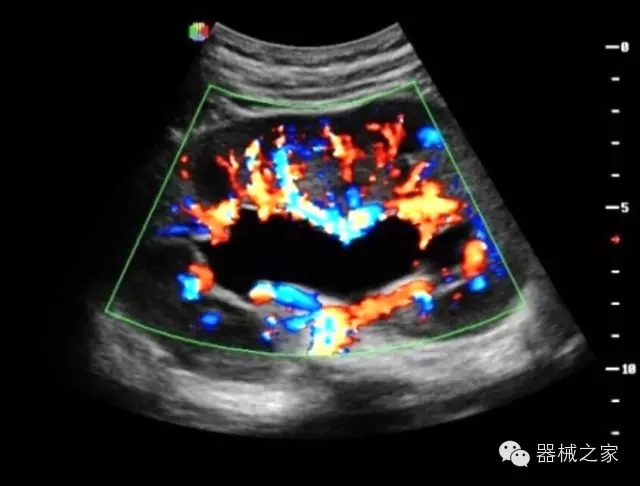

臨床圖片賞析